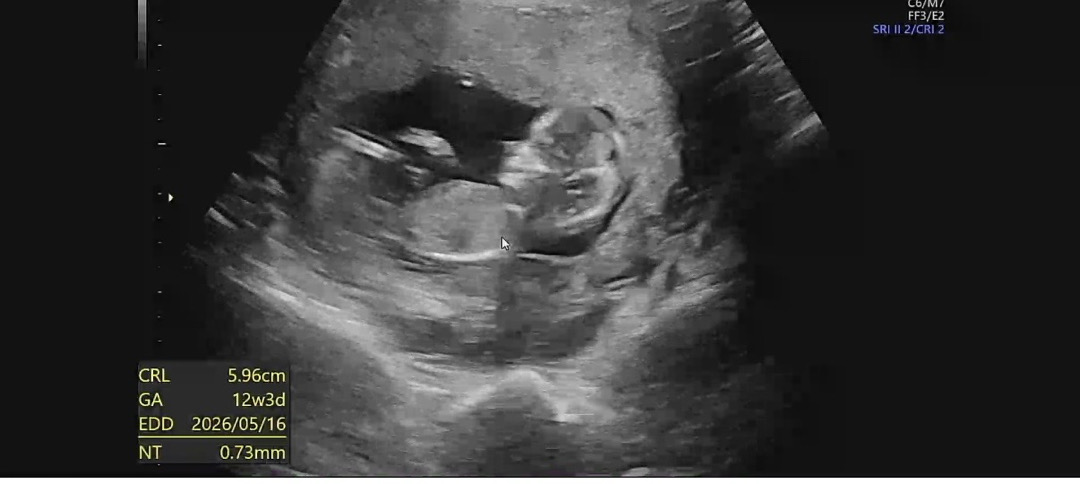

12주차 초음파입니다!!

각도법 모르겠어요ㅠㅠㅠ 초음파가 좀 흐릿하긴하네용